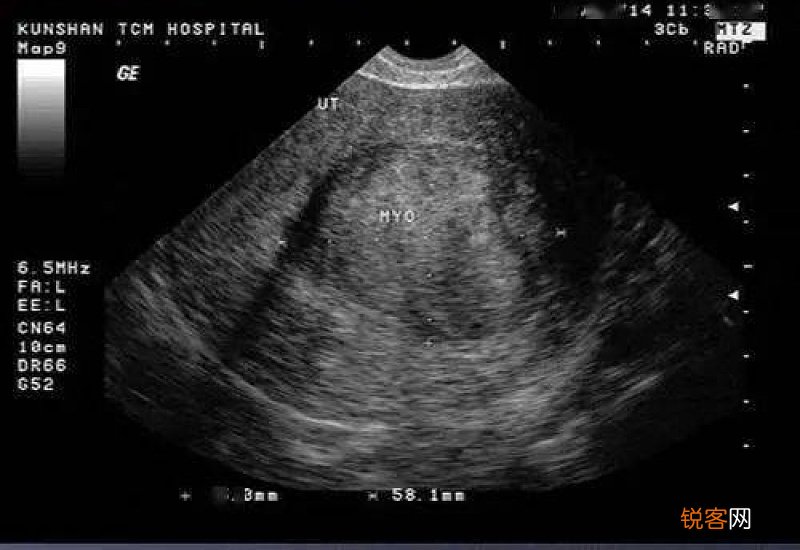

尿意不强烈一般建议等一等再去做b超,可以和护士说一下,让排在你后面的人先做 , 等你有尿意了再去做检查 。

因为做b超的时候 , 需要膀胱充盈,才能够让检查结果更加清楚,也能够避免膀胱内气体与子宫内气体发生重叠,造成的误诊、漏诊情况 。如果憋尿不充分,即便进去检查了,医生可能也会让你等一下再来 。